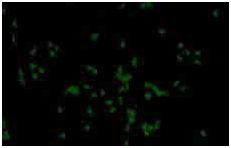

● 世界首例来源于人iPS 细胞的商业化胆碱类(Ach)神经细胞和AD 模型神经细胞

● 实验成像图显示体外培养的神经细胞与典型 AD 模型患者表型相同(β 淀粉样蛋白聚集)

高纯度(>80%)胆碱神经细胞